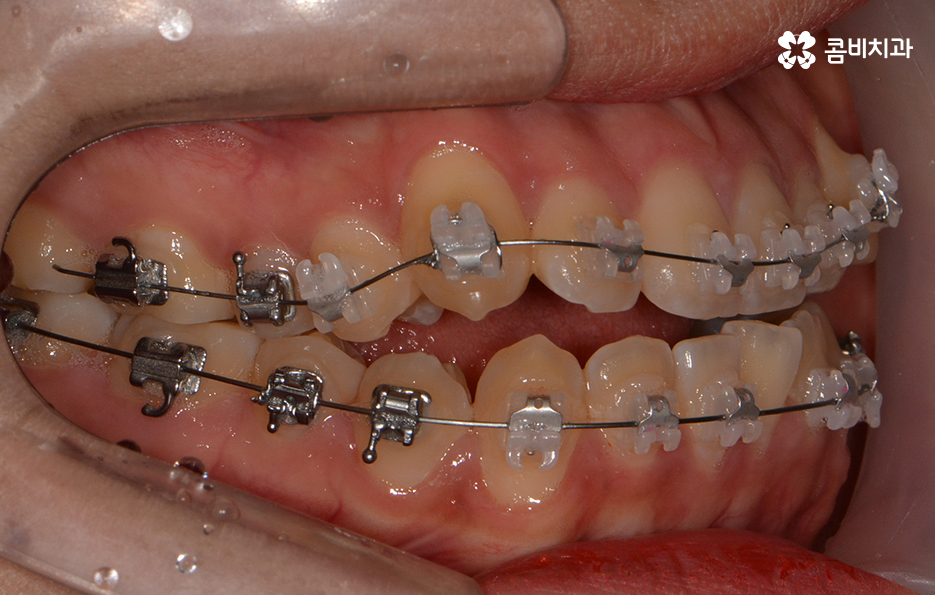

위 환자분의 경우에는 비발치로 송곳니 덧니 교정이

진행된 사례이며 전체 진료 기간은 약 1년 6개월가량이 소요되었습니다.

클리피씨 교정을 통해서 덧니가 개선되고 있는 경과

클리피씨 교정의 경우에는 일반적인 교정 방법에 비해서

진료 기간을 단축시킬 수 있다는 장점이 있는데

자가 결찰 장치로 서서히 치아를 지속적으로 이동시켜서

초기 통증은 줄이고 교정 기간의 단축이 가능합니다.

또한 교정 장치의 재질이 세라믹이기 때문에

심미적이라는 장점이 있으며 철사로 인한 찔림이